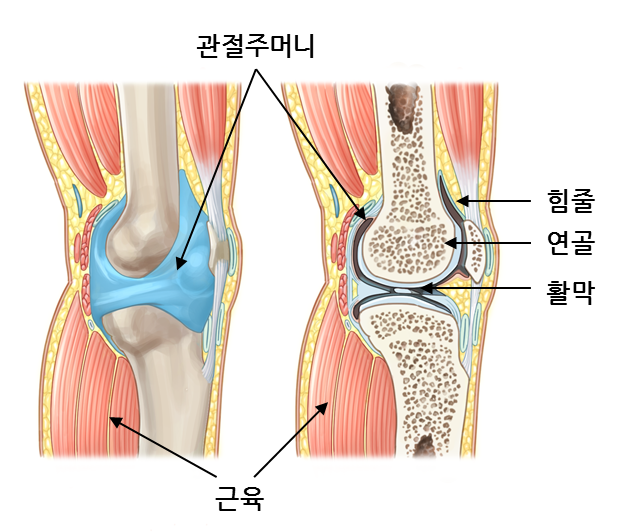

관절의 구조

관절을 둘러싸고 있는 구조는 크게 근육, 힘줄, 인대, 활막, 관절주머니, 연골 등으로 나눌 수 있습니다.

근육

관절을 지탱하고 움직일 수 있게 힘을 제공해줍니다.

힘줄

뼈와 근육을 연결해줍니다.

활막

활액을 분비하여 뼈와 뼈 사이의 마찰을 줄여줍니다.

관절주머니

윤활막을 둘러싼 주머니를 말하며 마찰을 감소시켜줍니다.

연골

뼈의 끝에 존재하며 무게를 지탱할 수 있게 하고 마찰을 감소시켜줍니다.